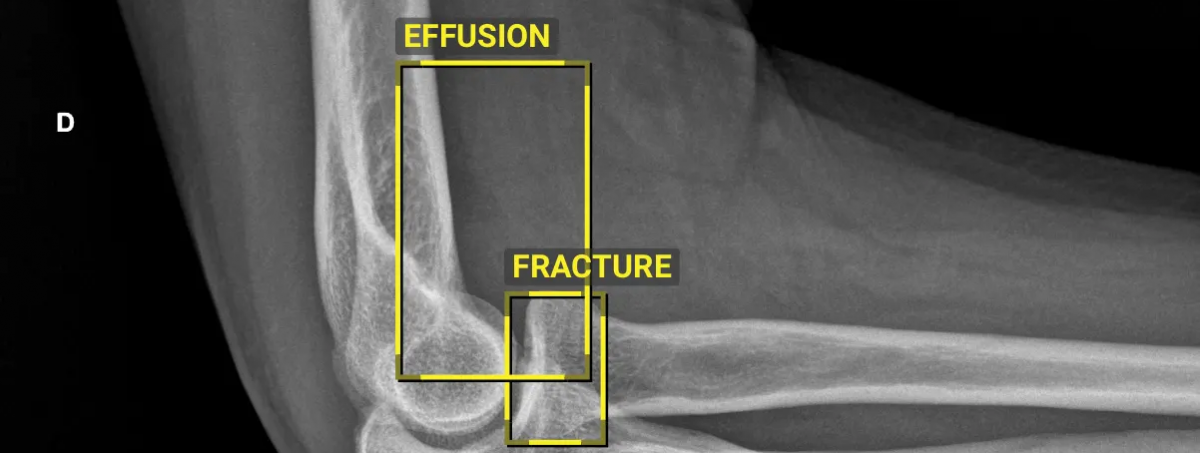

IT medical imaging company Sectra has rolled out its AI-driven fracture detection algorithm, BoneView, across all five Health and Social Care (HSC) Trusts in Northern Ireland according to a Healthcare Today article.

The deployment aims to support emergency departments and minor injury units in identifying bone fractures more accurately.

BoneView, developed in partnership with French AI firm Gleamer, follows a successful trial in the Northern Health and Social Care Trust. The evaluation demonstrated improved accuracy, with clinicians delivering correct diagnoses on first review, reducing the need for patient recalls once images were examined by specialist radiologists and radiographers.

The AI integration is part of the Northern Ireland Picture Archiving and Communication System (NIPACS+) enterprise imaging solution, one of the UK’s largest integrated diagnostic initiatives. BoneView is expected to aid in the examination of over 300,000 bone X-rays annually. Sectra is also exploring additional AI applications in areas such as chest X-rays and digital pathology, aiming to detect diseases and cancers earlier.